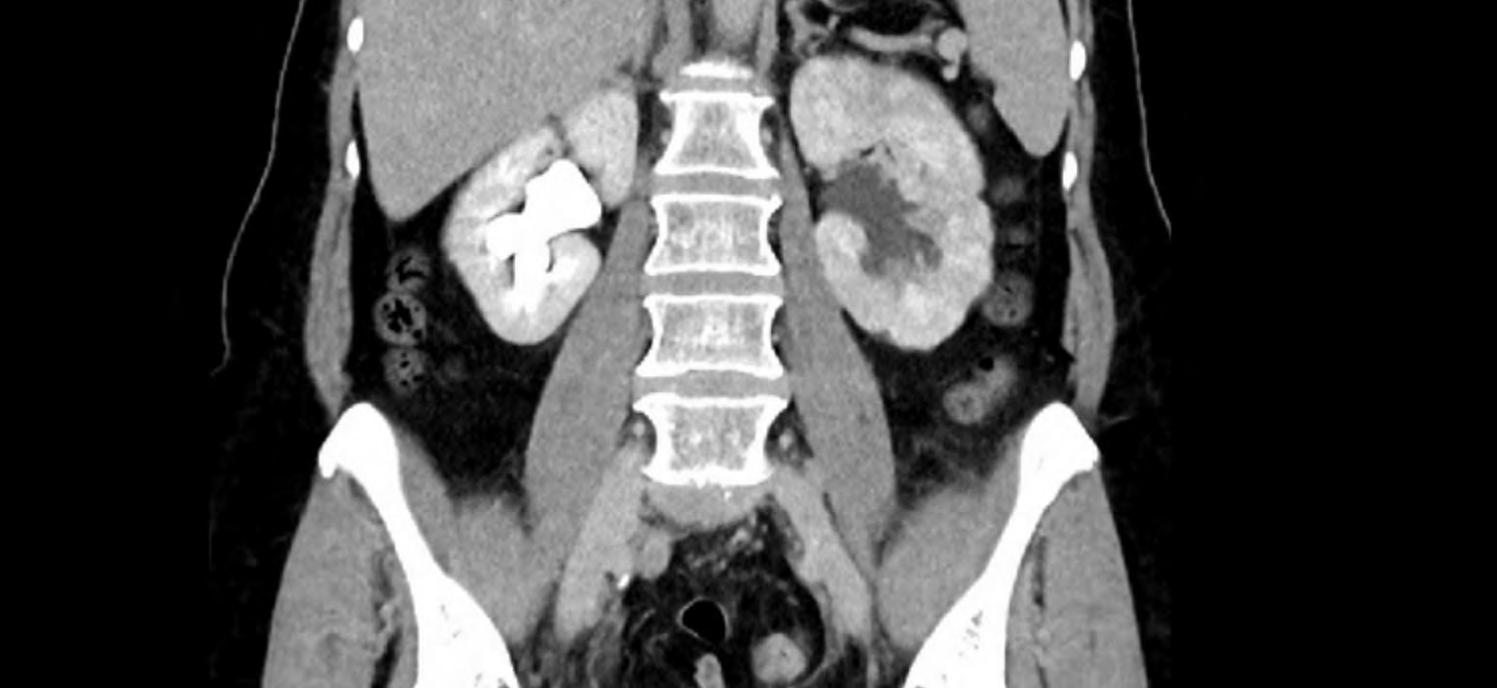

3.1.2 Zobrazovací metody Počítačová tomografie (CT – computed tomography) nebo magnetická rezonance (MR) břicha s cílením na nadledviny. Charakteristickým znakem maligních lézí je nízký obsah lipidů a vysoká hustota léze v CT obraze, nepravidelné okraje a rychlá progrese velikosti. Ke standardnímu CT/MR se přidávají nové funkční modality zlepšující přesnost diagnostiky.

PET s 11C-metomidátem (tracer zaměřený na enzymy kůry nadledvin) prokázal vysokou senzitivitu a specificitu pro záchyt ACC. Nově vyvíjený analog značený 18F (tracer [18F] CETO) překonává krátký poločas 11C a má vysokou specifitu – vykazuje vysokou akumulaci ve tkáni nadledvin při minimálním nespecifickém vychytávání v játrech. Tato metoda se jeví jako perspektivní pro přesnější odlišení ACC od benigních adrenálních nádorů v klinické praxi [9]. Pozitronová emisní tomografie v kombinaci s MR (PET/MR) je považována za užitečný a doporučovaný zobrazovací nástroj při diagnostice ACC u dětí, zejména z důvodů lepší detekce metabolicky aktivního tumoru a nižší radiační zátěže než u PET/CT.